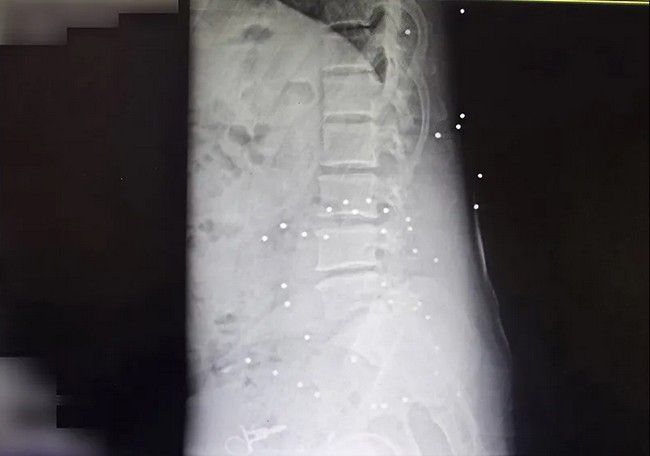

برخی از معترضان نیز با گلوله جنگی و به شکل مشخص از ناحیه اندام حیاتی هدف قرار گرفتهاند. در یکی از تصاویر رادیوگرافی گلوله یا ترکش در قفسه سینه و در ناحیه ریه مجروح دیده میشود، در تصویری دیگر گلوله جنگی در ناحیه تناسلی یک مرد قرار دارد و در موردی دیگر گلوله در نزدیکی ستون فقرات بیمار ثابت مانده است. کیانا کثیری در مورد عکس آخر میگوید: «در این عکس دو نوع آسیب را مشاهده میکنیم. یکی اصابت ناحیه پشت با گلوله جنگی، بر اساس ورود و قرار گرفتن گلوله به نظر میرسد که گلوله از بالا شلیک شده و آسیب دوم شکستگی سه مهره کمری،Lumbal Columna است که نیاز به ترمیم با فیکسیشنهای ارتوپدی داشته است.»